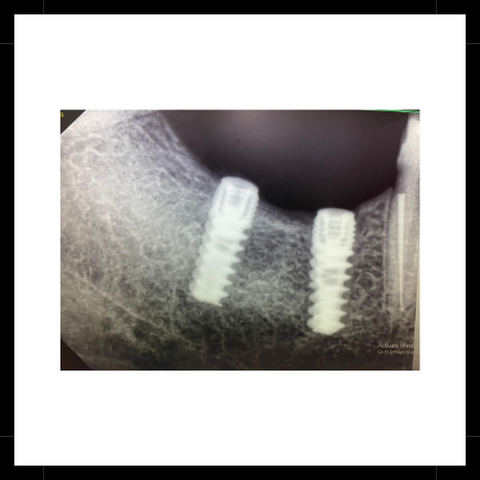

Implants Placed

Permanent replacement for missing teeth, providing a natural look & feel with long-lasting durability & improved oral function.